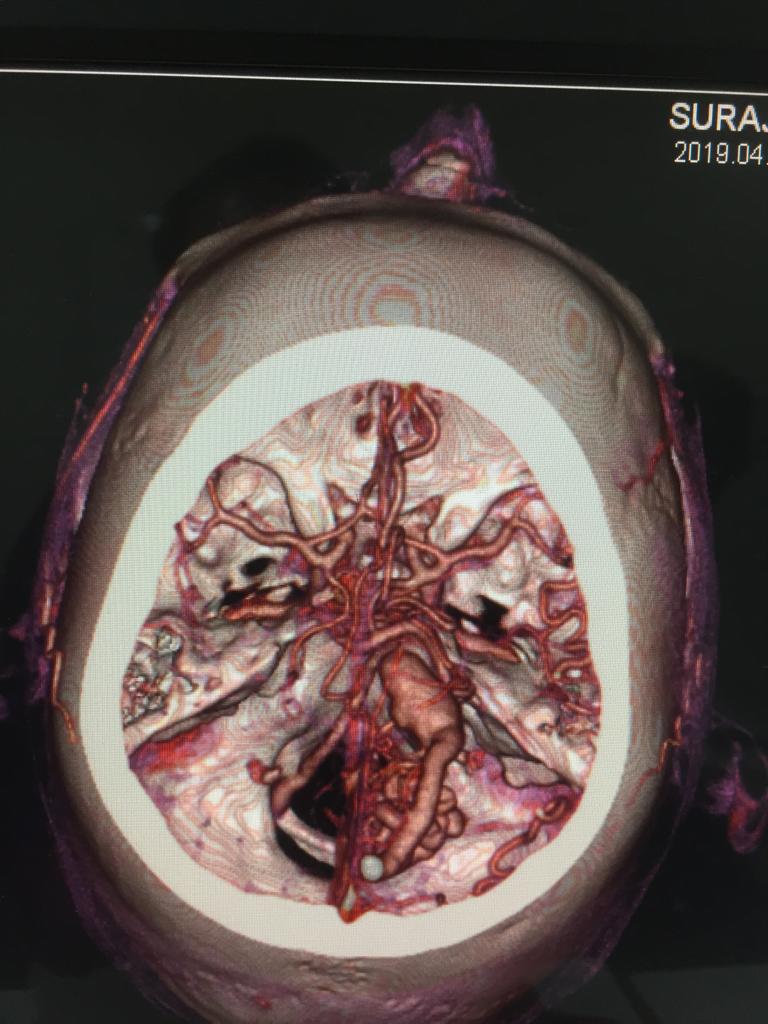

Cases